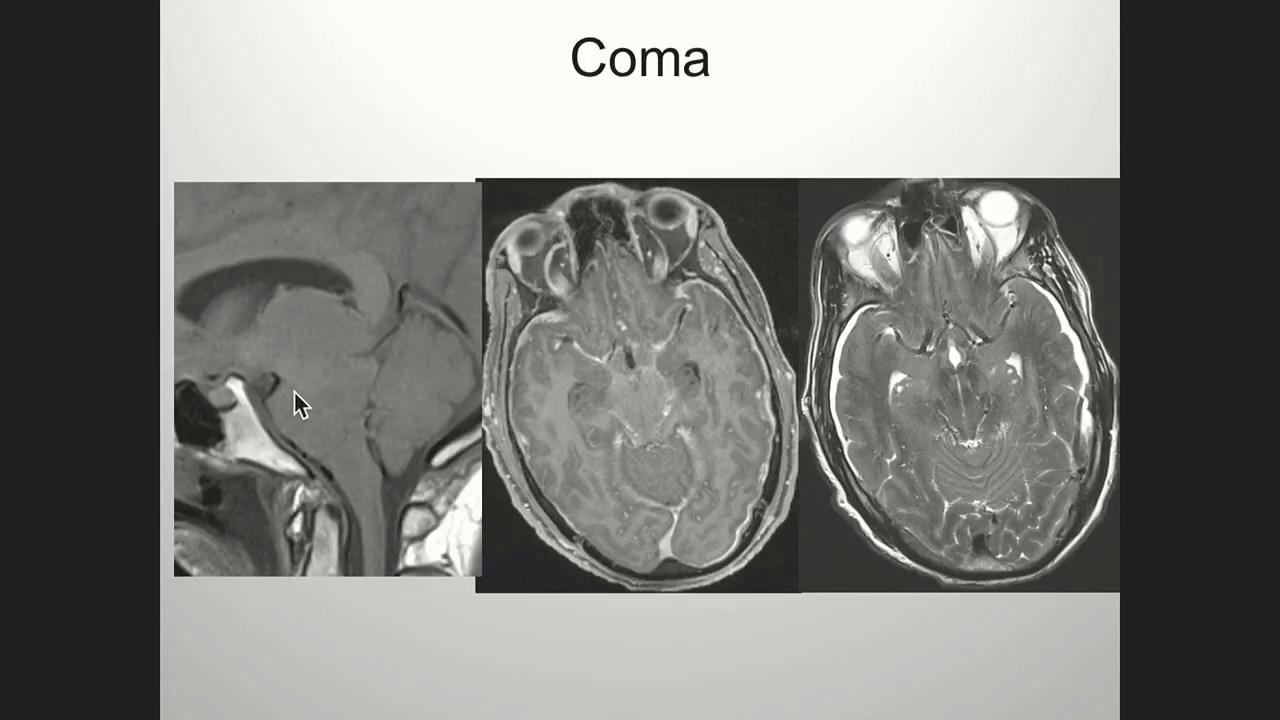

Serious Complications of Intracranial Hypotension